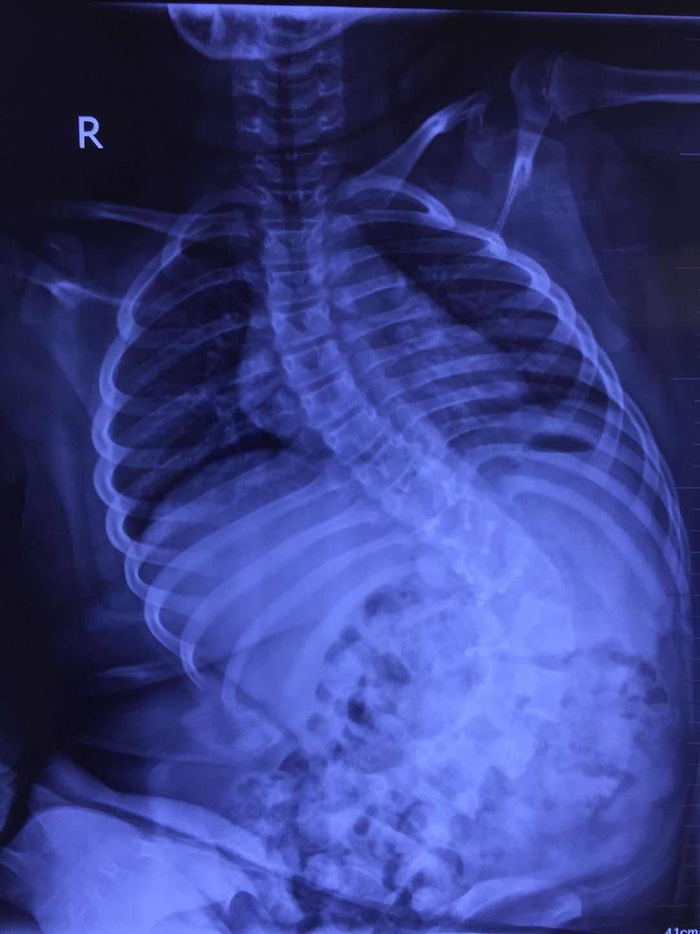

郭晓东提供的影像学资料显示,下腰瘫痪后的孩子脊柱弯成了这样。'>郭晓东提供的影像学资料显示,下腰瘫痪后的孩子脊柱弯成了这样。